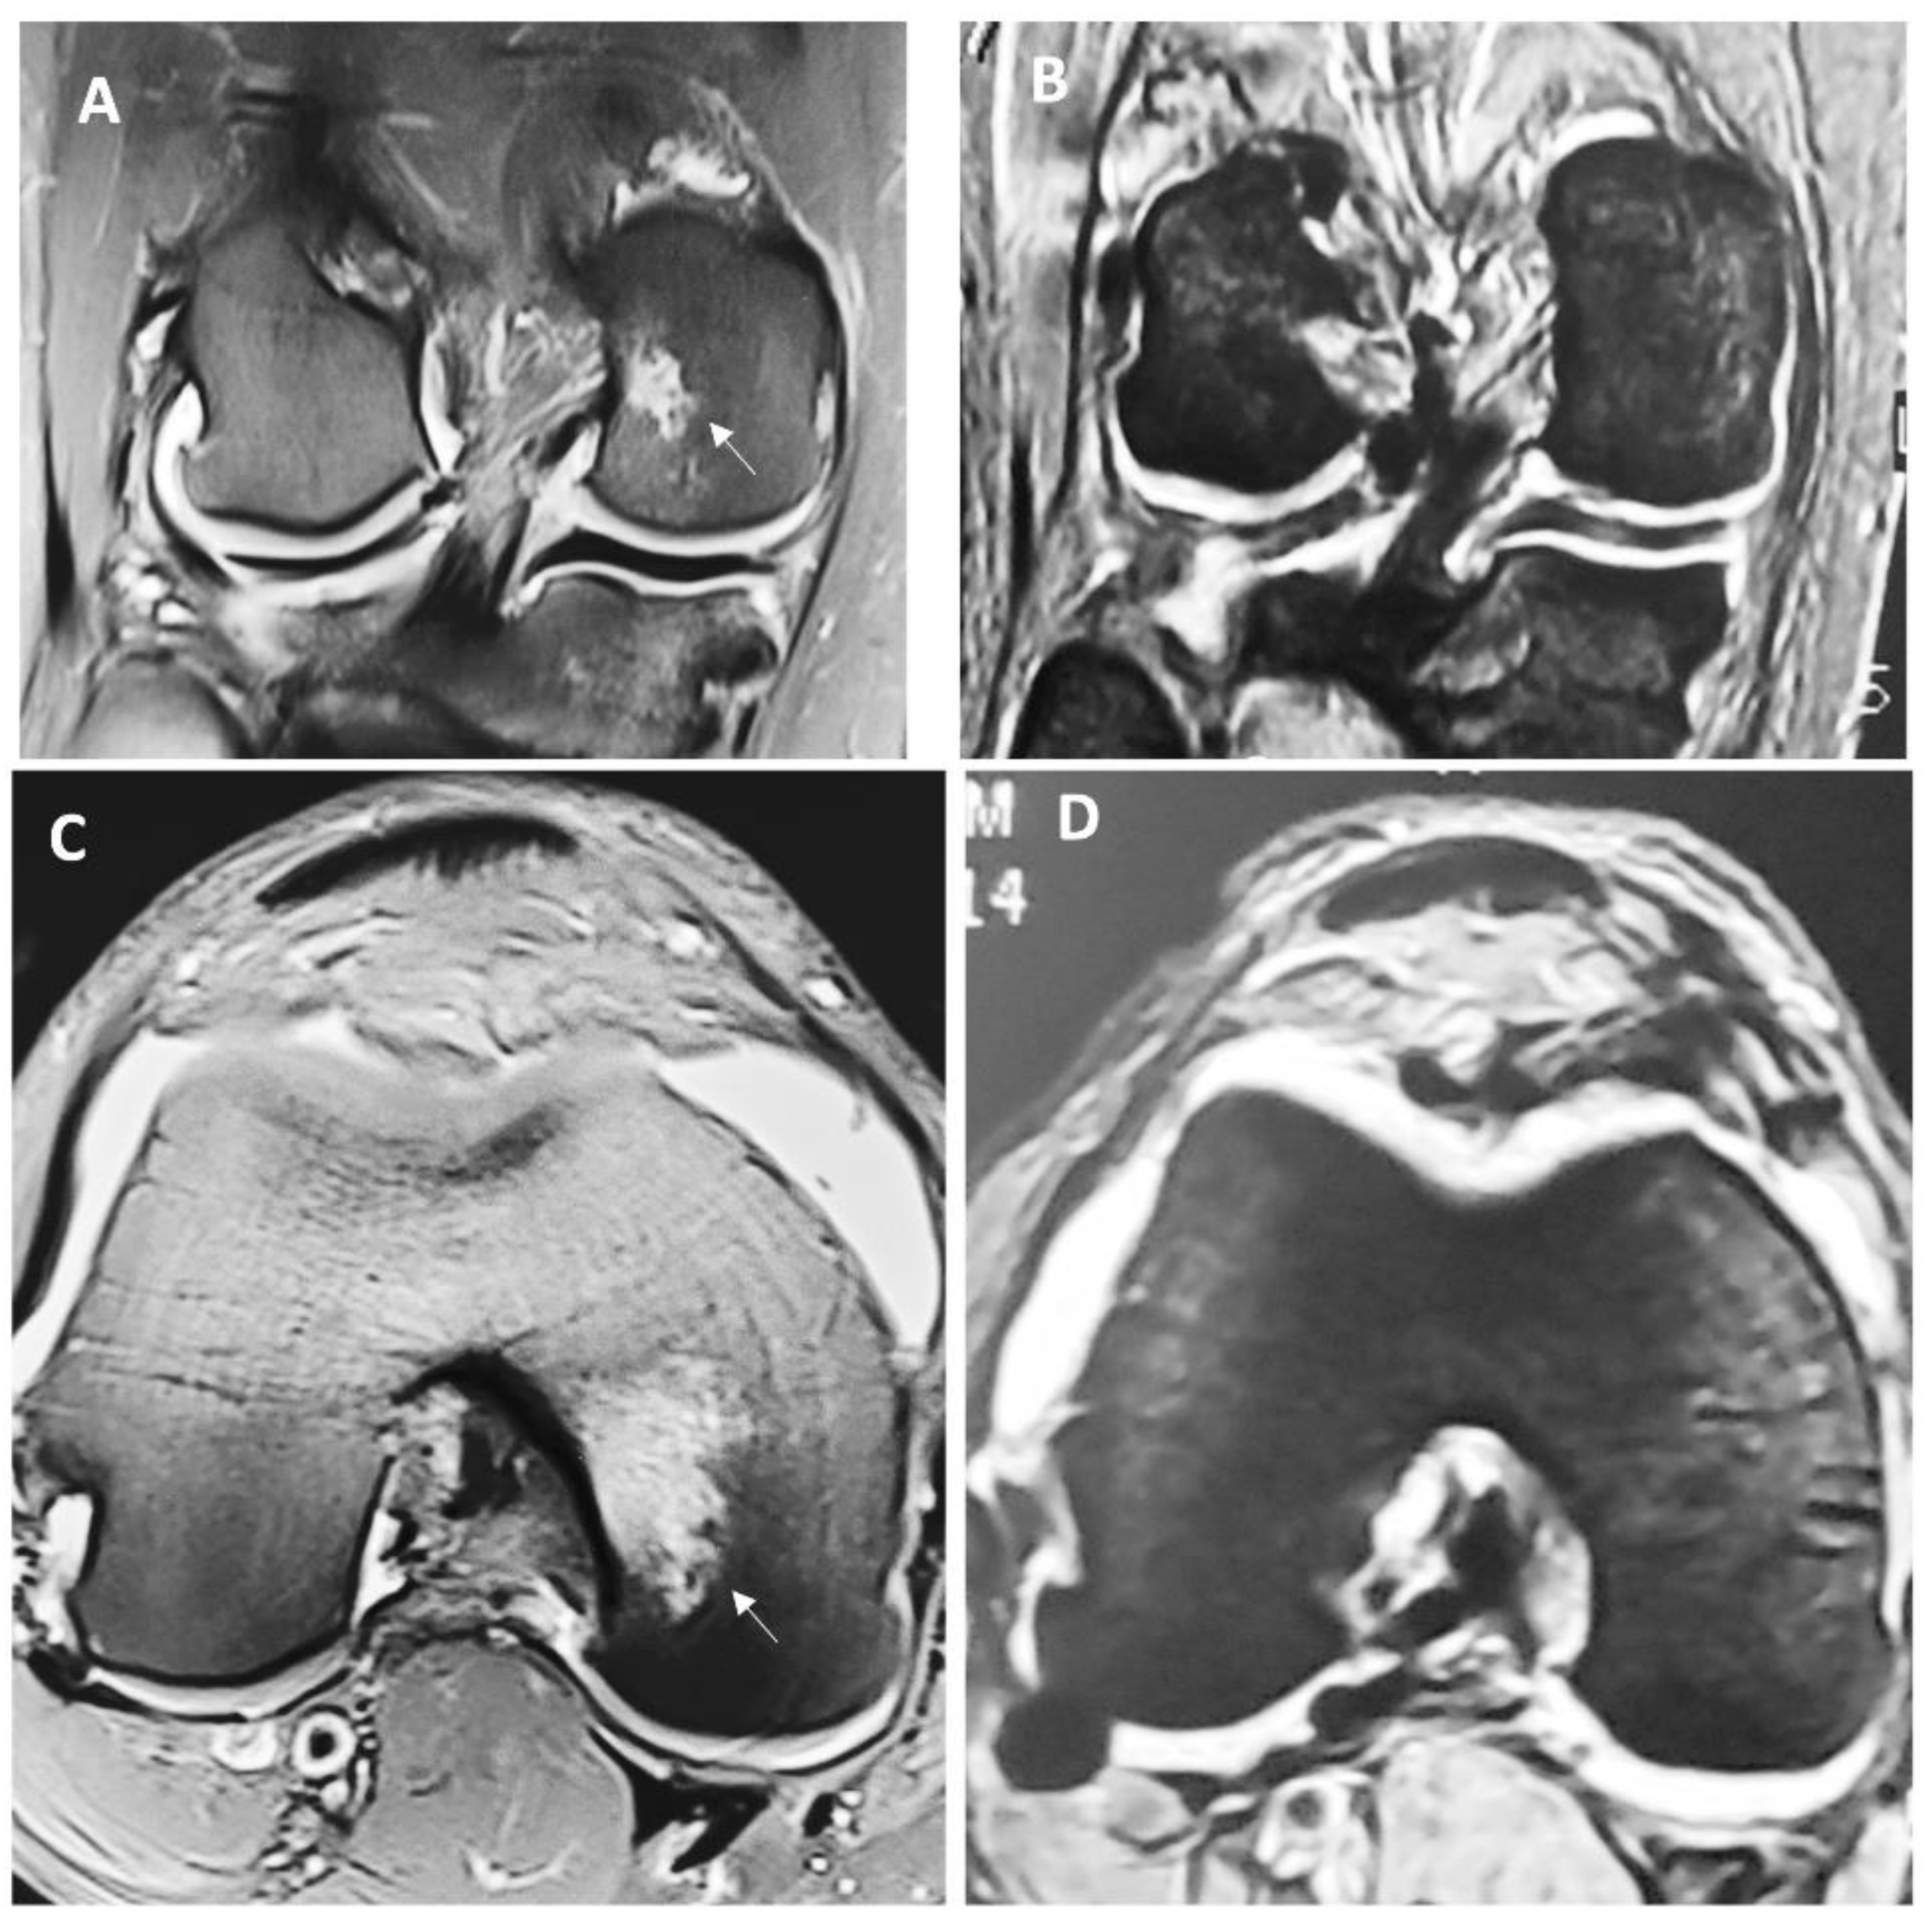

Figure 1. Representative MRI view of the full-thickness cartilage defect and adjacent tissue before (A and C) and 6 months after the surgery (B and D) in a patient treated with HA 3-D fold scaffold. Letters A and B anteroposterior views with a lesion in the medial femoral condyle (arrow), in the same view 6 months after, this lesion has visually disappeared and replaced with reparative tissue. Letters C and D are coronal views of the lesion located in the same anatomical structure with evident subchondral edema, which disappears 6 months after the surgery.

With respect to surgery and the immediate postoperative period, there were no significant complications reported for any patient. After 6 months of the surgery patients were asked to undergo a new MRI to assess changes in the Henderson scale, a statistically significant improvement was found in the group treated with the 3-D scaffold to a median (ICR) of 1 (1-1.5) (p<0.001), which was not evident in the microfractures treated group.

Figure 1 depicts macroscopic changes observed at 6 months in the MRI. Then, at 12 months after the surgery, there was a continued improvement for both groups, but this difference was markedly important for individuals in the HA 3-D scaffold group, since all patients from this group were found to have a Henderson scale of 1, while the group treated with microfractures still had almost half of the individuals (47.6 %) with a score of 2 (p 0.0048). This means that all patients treated with the HA 3-D scaffold returned to a radiographic image that represents a knee with absence of fluid and edema in the joint. Conversely, in the microfractures group, this was not achieved by any patient. Table 2 represents these comparisons between groups.